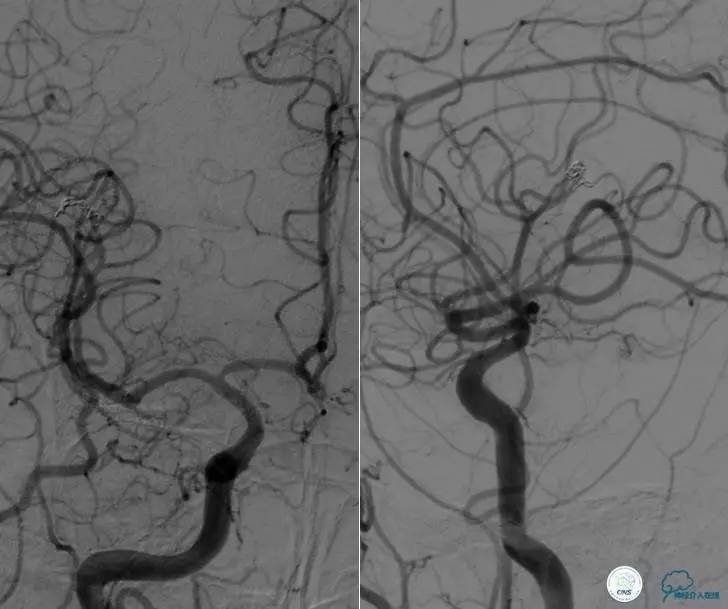

▼DSA示右侧椎动脉发育低下,弥漫性狭窄,可以看到左侧椎动脉反流,因此判断左侧椎动脉V4段CTO。

微导丝穿过闭塞段,微导管造影,球扩闭塞段,置入Wingspan支架,血流完全恢复正常。

患者术后2天再次出现卒中发作,药物治疗好转,此后病情稳定。半年后复查DSA,见支架闭塞,侧支循环开放。患者一般情况好,mRS:1分。